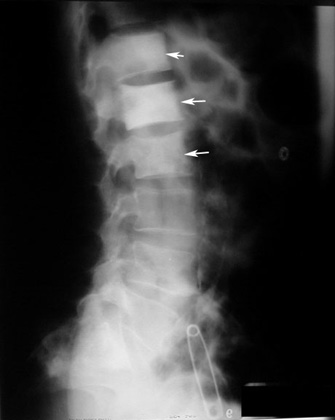

Как выглядит опухоль позвоночника на рентгеновских снимках